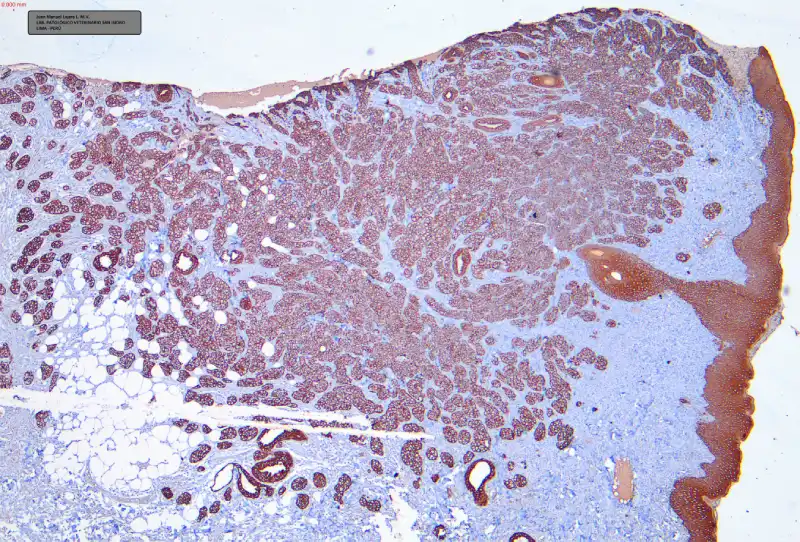

Los resultados fueron conversados con el equipo de la clínica y consultados con el oncólogo veterinario. Se decidió realizar estudios de INMUNOHISTOQUÍMICA confirmatorios para iniciar el tratamiento. Para la confirmación se optó por el marcador de Citoqueratina (CK) el cual brindó una reacción positiva intensa con las células tumorales del tejido (Foto C 1-2)

FOTO C-1

FOTO C-2